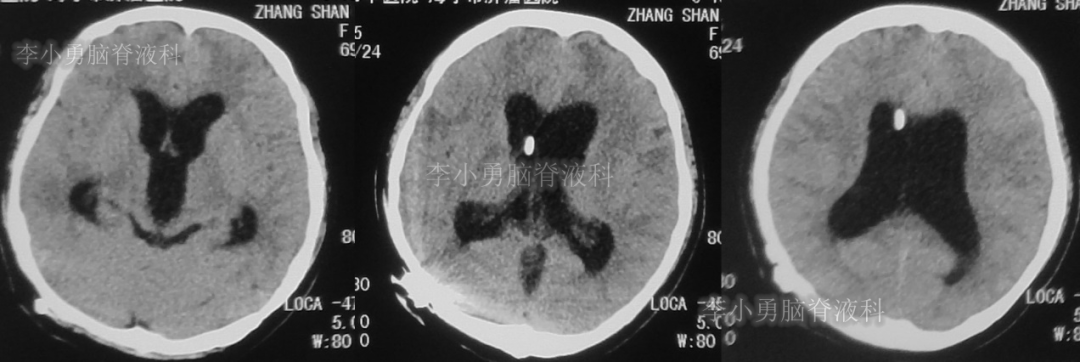

患者于2018年1月29日,突发头痛、头晕、恶心、呕吐,并高热40度。在当地医院门诊输入4天抗生素后发热缓解,但出现了双眼不能上视(眼球不能向上看)。5天后即2018年2月3日,在当地的第1家医院:浙江省海宁市某医院行头颅CT(图-1)发现脑室扩张,当地医院诊断为“梗阻性脑积水”。

图-1:2018年2月3日头颅CT

又2天后,即2018年2月5日,为求更好的治疗,患者转到第2家医院:浙江省杭州市的某三甲医院就诊,行头颅增强核磁共振检查(图-2)提示双侧脑室及第三脑室扩张,中脑导水管形态消失,第四脑室无扩张,未见颅内占位病变。

图-2:2018年2月5日头颅核磁